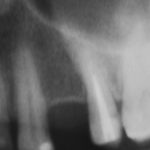

Для этого мы сделали КЛКТ:

И КЛКТ показала нам, что с имплантатами и окружающей костью всё зашибись. Через 12 лет после операции, отсутствия наблюдения, пофигизма в замене временных коронок! Нужны ли тебе еще какие-нибудь доводы в пользу долгосрочной эффективности метода?